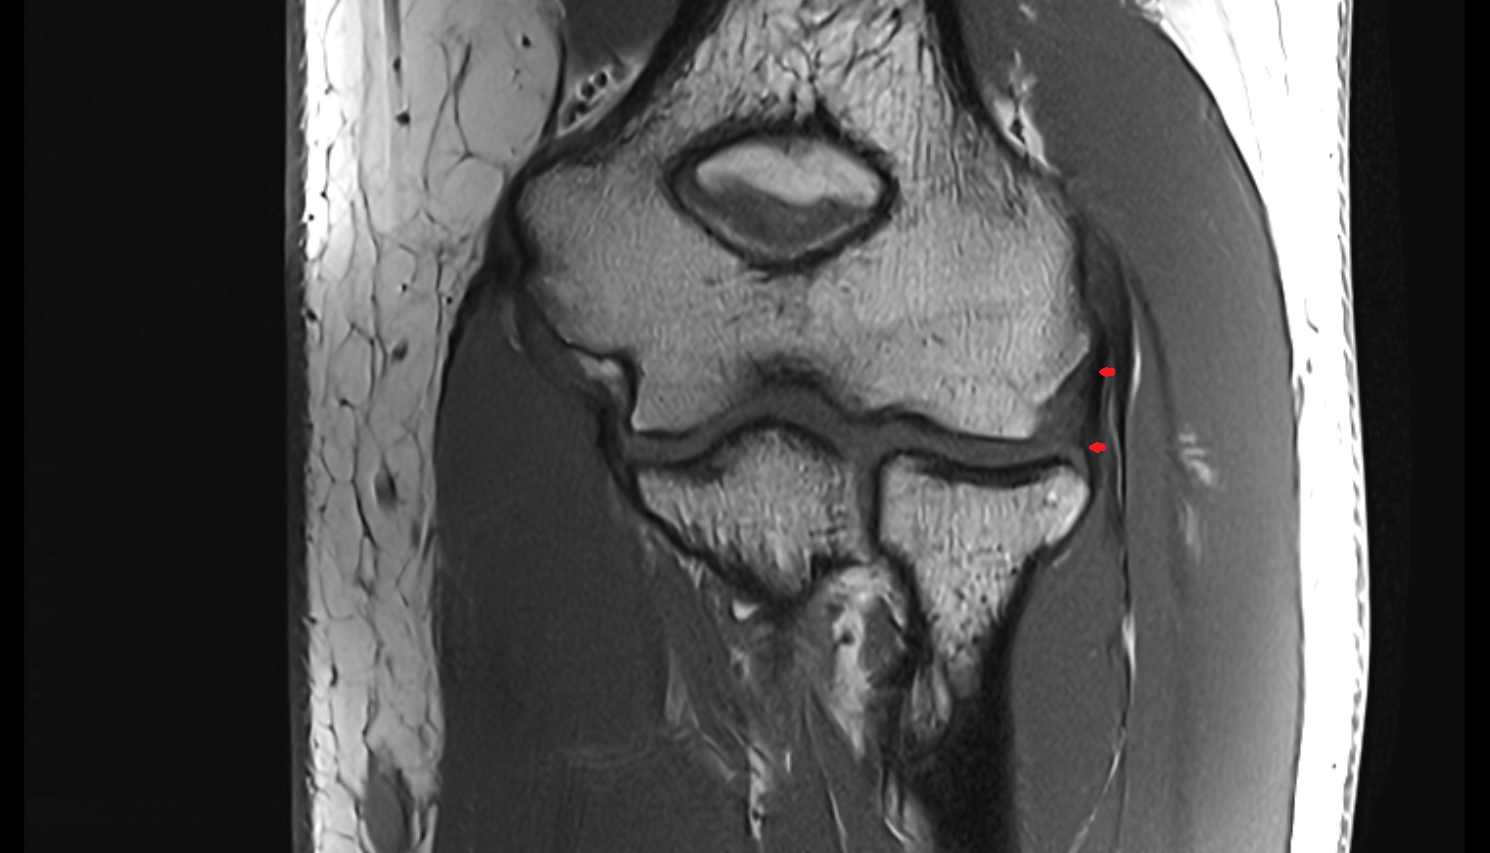

- Medial collateral ligament

- Medial meniscus

- Lateral meniscus